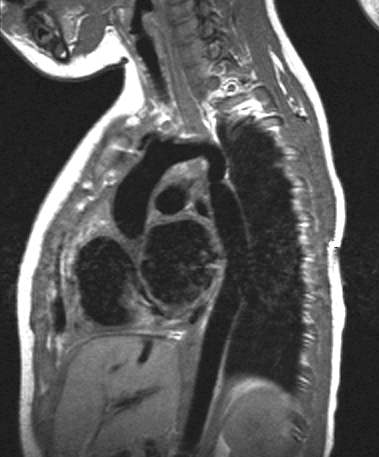

Scott WilliamsMusculoskeletalPost-operative Bone Scanning:April 2, 2002MusculoskeletalMetabolic Bone Disease:April 2, 2002Vascular AbnormalitiesVascular > Coarctation > Images > Case1April 2, 2002CongenitalCongenital > CF > Images > Cf1April 2, 2002PETPET > PET CNS imagingApril 2, 2002AutoimmuneAutoimmune > SarcoidApril 2, 2002PETPET > PET tumor imaging > GeneralApril 2, 2002Miscellaneous PulmonaryMisc > Transplant > Images > Transplant1April 2, 2002Tumor ImagingTechnetium-99m Sestamibi Tumor Imaging:April 2, 2002Mediastinal MassesMediastinum > PheochromocytomaApril 2, 2002Previous PagePage 139 of 265Next PageTop StoriesMolecular ImagingPET reveals mechanism underlying brain fog in long COVIDBrain regions where C-11 K-2 radiotracer was increased were negatively correlated with long COVID patients’ performance on cognitive tests.MRIMRI finds that brain shape changes may be associated with dementiaWomens ImagingFalse-positive DBT findings differ between AI, radiologistsPractice ManagementWhat is the real impact of the 2025 MPFS Proposed Rule on radiology practices?Sponsor ContentDigital Innovations Shaping the Future of Radiology